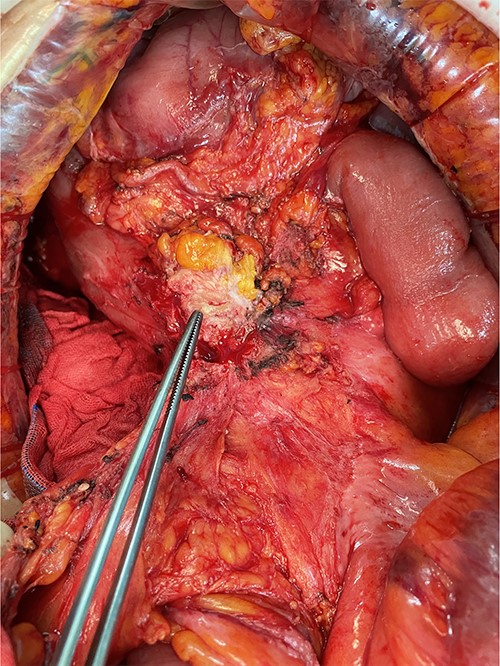

We made an incision avoiding the tumor. The patient’s abdominal cavity showed overall adhesion due to previous surgery. We found tumor invading or being adherent to the duodenum and superior mesenteric vein (Fig. 3). We thought that superior mesentery vein (SMV) collapsed due to compression, but it was identified completely occluded due to invasion. We also found that jejunal first branch was very dilated due to obstruction (Fig. 4). We performed completion right hemicolectomy with duodenal segmental resection, SMV resection and anastomosis (Fig. 5). Anterior resection was performed for the accompanying sigmoid colon cancer.

Tumor invaded or was adherent to the duodenum and superior mesenteric vein.